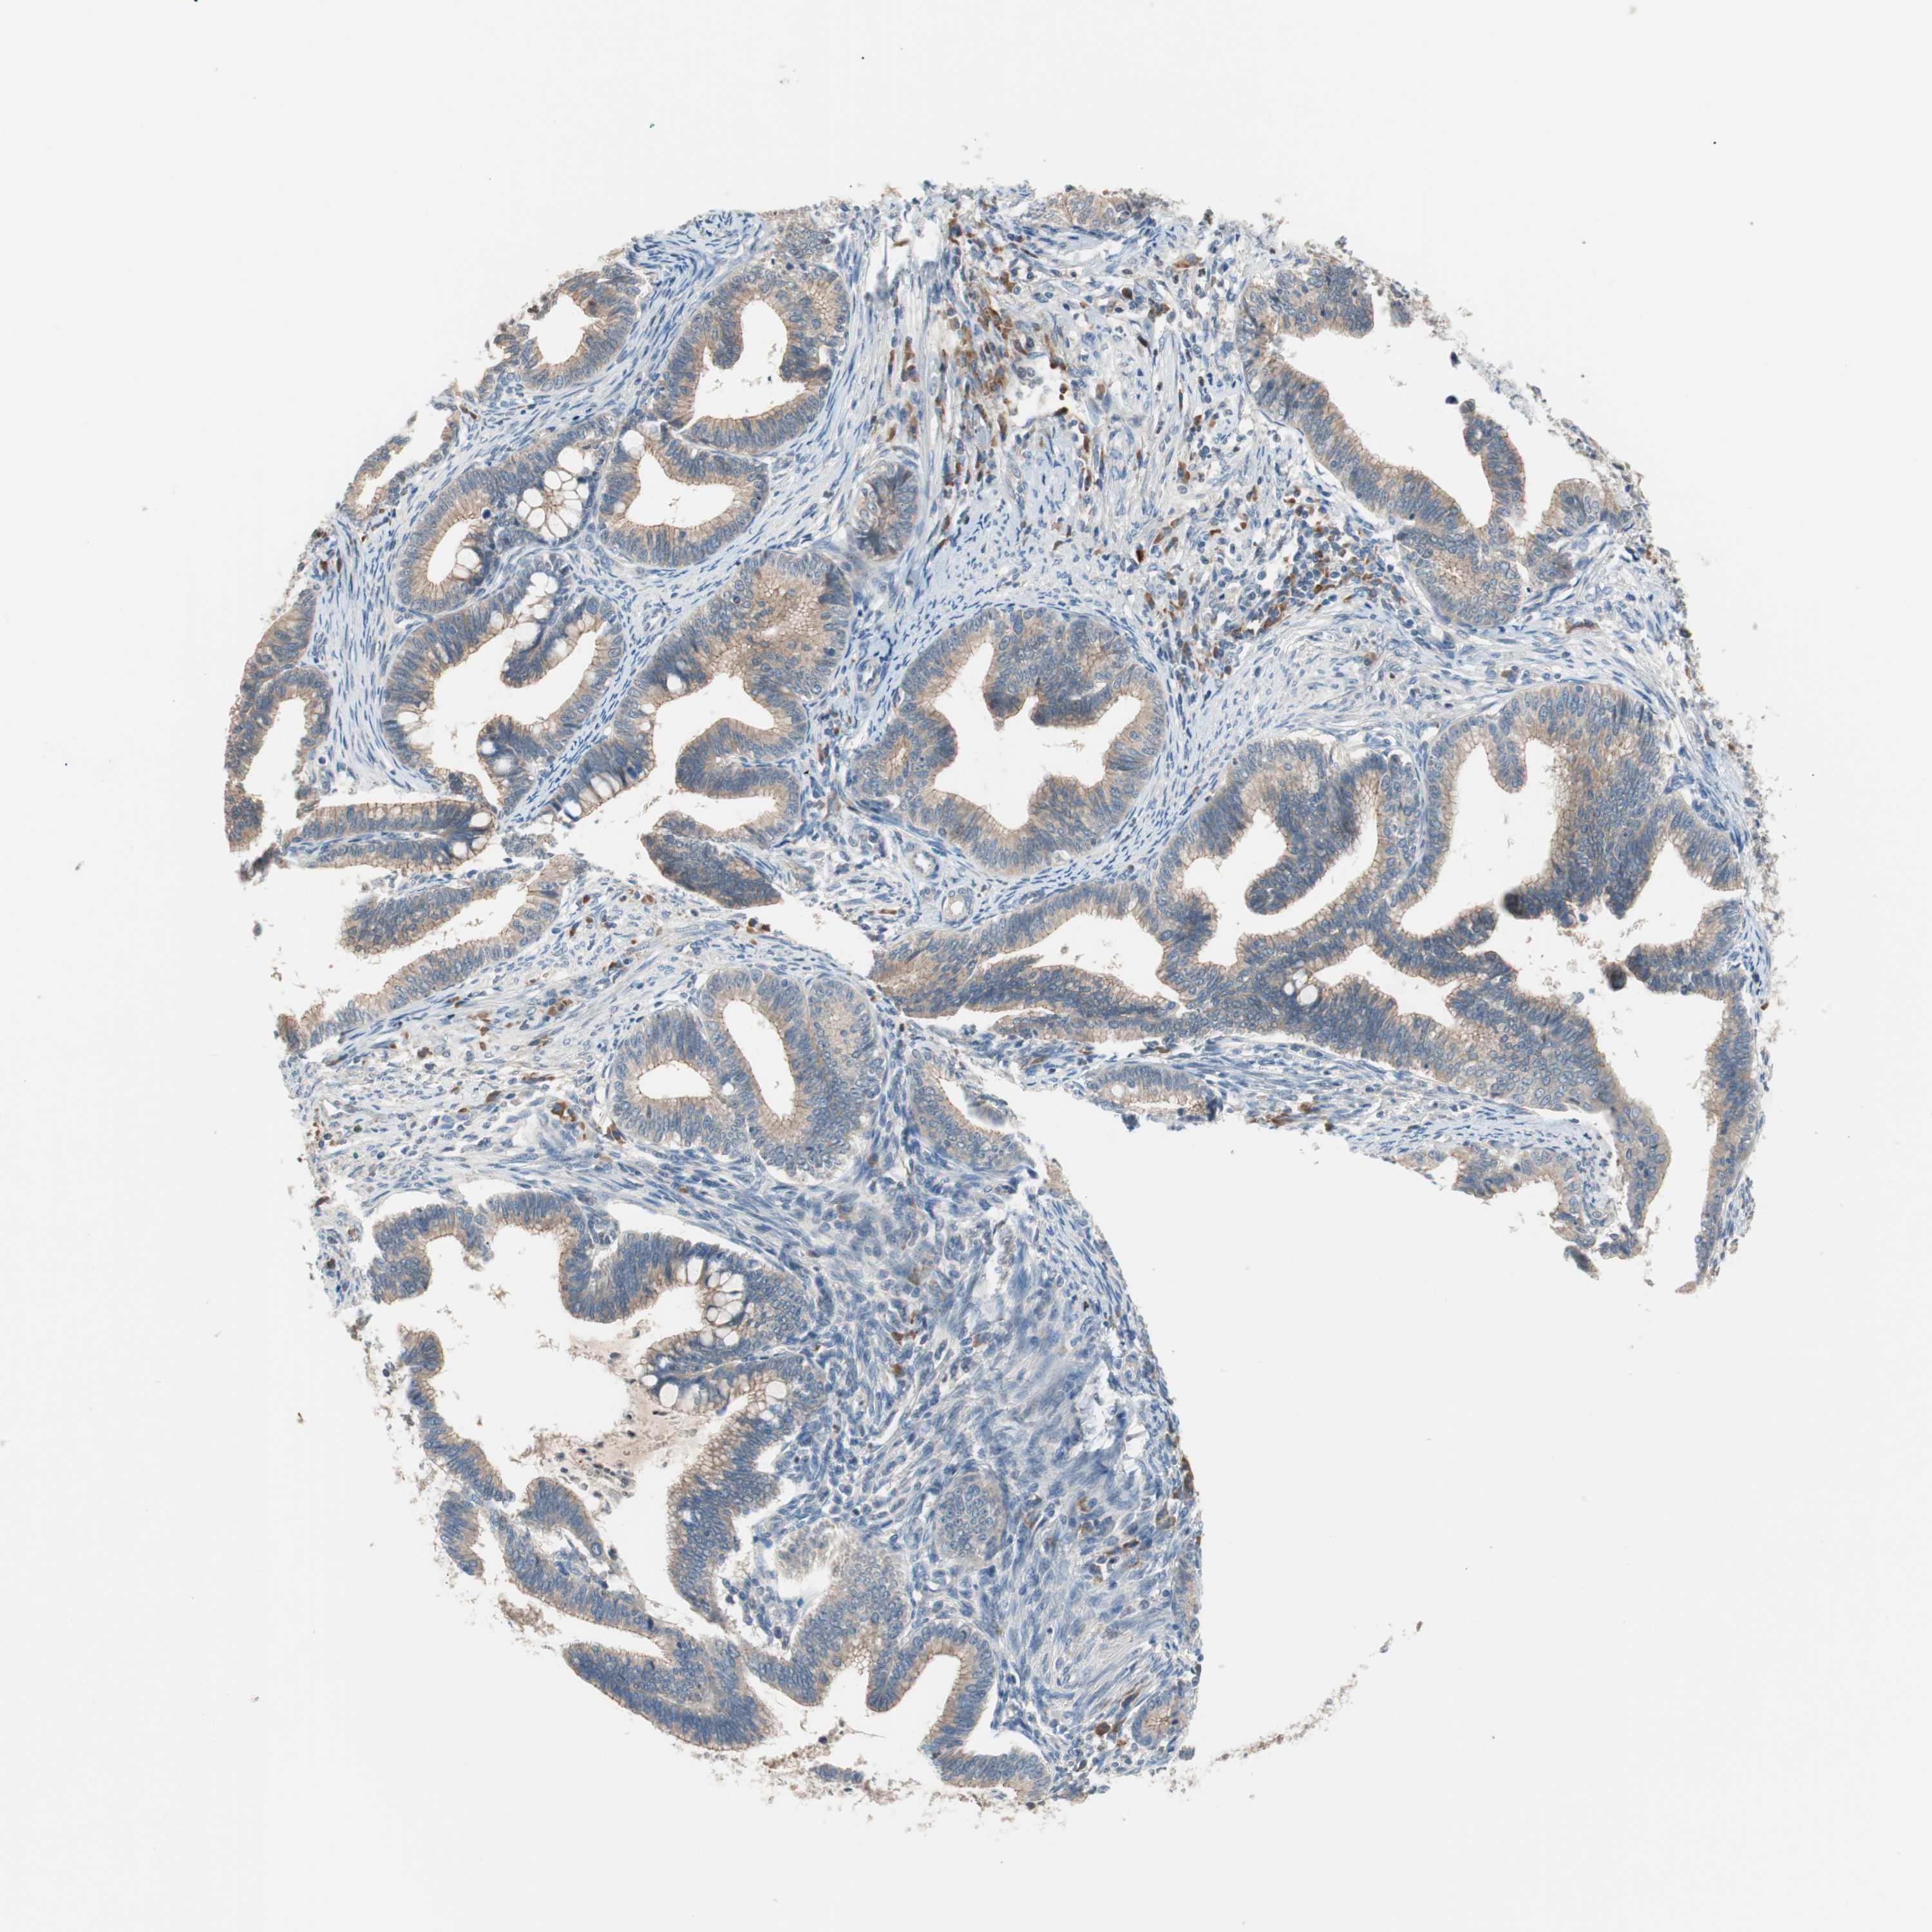

CERVICAL CANCER - Protein expressioni

A mouse-over function shows sample information and annotation data. Click on an image to view it in a full screen mode. Samples can be filtered based on level of antibody staining by selecting one or several of the following categories: high, medium, low and not detected. The assay and annotation is described here.

Note that samples used for immunohistochemistry by the Human Protein Atlas do not correspond to samples in the TCGA dataset.

Antibody stainingi

Antibody staining in the annotated cell types in the current human tissue is reported as not detected, low, medium, or high, based on conventional immunohistochemistry profiling in selected tissues. This score is based on the combination of the staining intensity and fraction of stained cells.

Each image is clickable and will lead to virtual microscopy that enables deeper exploration of all samples and also displays staining intensity scores, fraction scores and subcellular localization as well as patient and tissue information for each sample.

Antibody HPA006277

Antibody HPA006507

Antibody CAB017027

Staining

High

Medium

Low

Not detected

Intensity

Strong

Moderate

Weak

Negative

Quantity

>75%

75%-25%

<25%

None

Location

Nuclear

Cytoplasmic/membranous

Cytoplasmic/membranous,nuclear

Squamous cell carcinoma, NOS

Adenocarcinoma, NOS